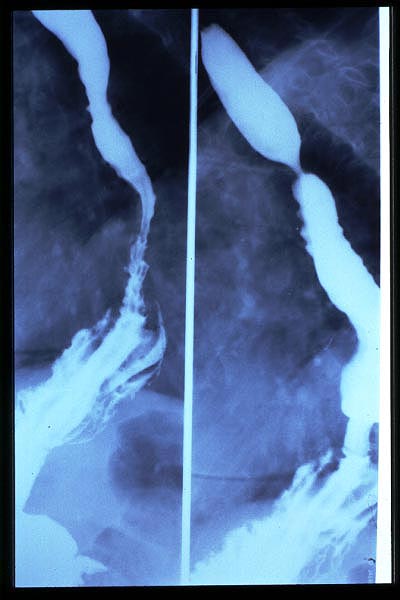

Ondas terciarias, HH